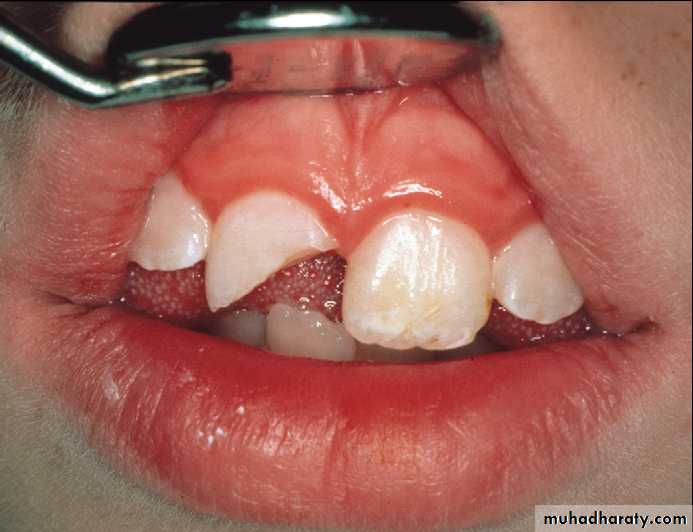

Incisors with crown-root fractures